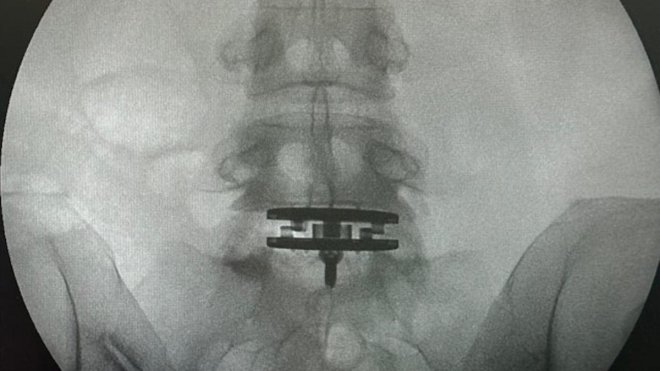

曝光多張X光照片以及與醫護人員的合照,她躺在手術台上自拍,透露她接受醫師的建議進行椎間盤置換手術,更指出,這次手術是她生完女兒後最重要的手術,期盼術後能繼續做她最喜愛的運動。

從畫面中來看,徐濠縈已順利完成手術,目前正在家中休養,女兒陳康堤也為母親加油,貼文曝光後,大批網友為她留言祝福,紛紛表示:「很難想像妳下背有如此大的負擔,仍然堅持自己的夢想,祝福徐手術順利,讓妳能做更多想做的事」、「你同Eason一起加油」、「和臣臣(陳奕迅)一起加油,好好休養哦,快點好起來」